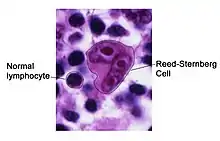

Hodgkin lymphoma (HL) is a type of lymphoma in which cancer originates from a specific type of white blood cell called lymphocytes, where multinucleated Reed–Sternberg cells (RS cells) are present in the patient's lymph nodes.[2][8] The condition was named after the English physician Thomas Hodgkin, who first described it in 1832.[9][10] Symptoms may include fever, night sweats, and weight loss.[2] Often, nonpainful enlarged lymph nodes occur in the neck, under the arm, or in the groin.[2] Those affected may feel tired or be itchy.[2]

Microscopic examination of the lymph node biopsy reveals complete or partial effacement of the lymph node architecture by scattered large malignant cells known as Reed-Sternberg cells (RSC) (typical and variants) admixed within a reactive cell infiltrate composed of variable proportions of lymphocytes, histiocytes, eosinophils, and plasma cells. The Reed–Sternberg cells are identified as large often bi-nucleated cells with prominent nucleoli and an unusual CD45−, CD30+, CD15+/− immunophenotype. In approximately 50% of cases, the Reed–Sternberg cells are infected by the Epstein–Barr virus.[39]

Characteristics of classic Reed–Sternberg cells include large size (20–50 micrometres), abundant, amphophilic, finely granular/homogeneous cytoplasm; two mirror-image nuclei (owl eyes) each with an eosinophilic nucleolus and a thick nuclear membrane (chromatin is distributed close to the nuclear membrane). Almost all of these cells have an increased copy number of chromosome 9p/9p24.1.[40]

Variants:

- Hodgkin cell (atypical mononuclear RSC) is a variant of RS cell, which has the same characteristics but is mononucleated.[41]

- Lacunar RSC is large, with a single hyperlobulated nucleus, multiple, small nucleoli and eosinophilic cytoplasm which is retracted around the nucleus, creating an empty space ("lacunae").

- Pleomorphic RSC has multiple irregular nuclei.

- "Popcorn" RSC (lympho-histiocytic variant) is a small cell, with a very lobulated nucleus, small nucleoli.

- "Mummy" RSC has a compact nucleus with no nucleolus and basophilic cytoplasm.